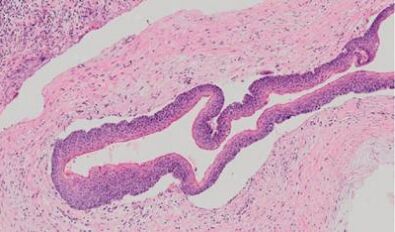

21.病患環口X光攝影顯示有多發性之顎骨破壞區域,各區域切片檢查的發現均見如下圖之病變,則下列何者為最可能之診斷? (A)唐氏症(Down syndrome) (B)伊格爾症候群(Eagle syndrome) (C)克新氏症候群(Cushing syndrome) (D)戈林症候群(Gorlin syndrome)